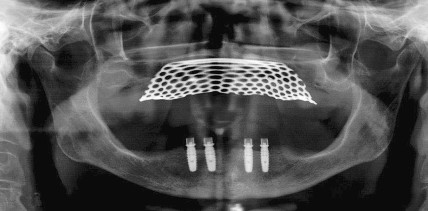

Implantatgestützte Locator®-Prothese zur Versorgung zahnloser Kiefer

Jahr 2017, Ausgabe 01-02, Seite 32 Autoren: Dr. Dr. Manfred Wolf, Dr. Daniel Rein

Implantatgetragene Prothese zur Versorgung zahnloser Kiefer

Jahr 2014, Ausgabe 07_08 Implantologie, Seite 24 Autoren: Dr. Dr. Manfred Wolf, Dr. Daniel Rein